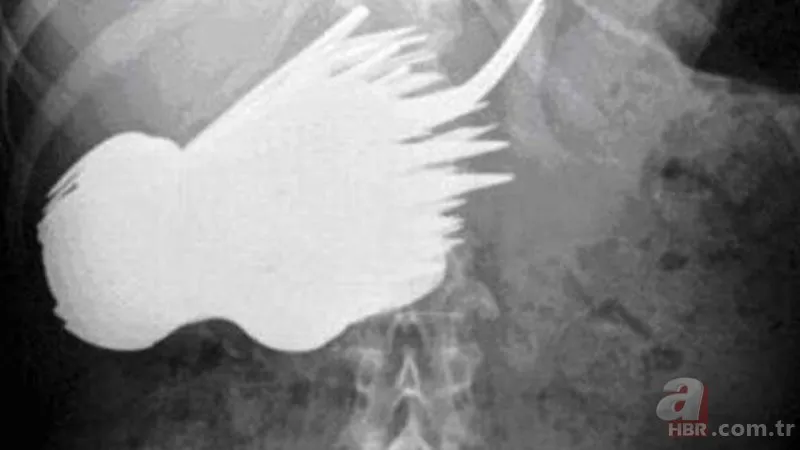

Tutuklular, hastaneye gidebilmek ya da hapishaneye kaçak olarak sokabilmek için bazen çok acayip şeyler yutabiliyor. Amerika'nın Kuzey Karolina eyaletindeki bir hapishanede bulunan tutuklular, hastaneye gönderilme umuduyla pil ve yatak yayı yutmuşlar. Her iki tutuklu da denemesinde başarılı oldu; yukarıda, karın ağrısı şikayetiyle gittikleri hastanede çekilen röntgenleri görüyorsunuz.